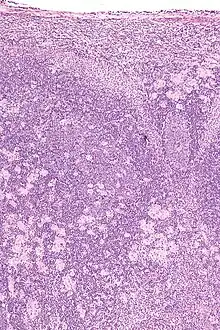

Real-time PCR is useful in pathogen detection, gene expression and regulation, and allelic discrimination. This PCR technique utilizes the 5' nuclease activity of Taq DNA polymerase to cleave a nonextendible, fluorescence-labeled hybridization probe during the extension phase of PCR.[63] A second fluorescent dye, e.g., 6-carboxy-tetramethyl-rhodamine, quenches the fluorescence of the intact probe.[63] The nuclease cleavage of the hybridization probe during the PCR releases the effect of quenching resulting in an increase of fluorescence proportional to the amount of PCR product, which can be monitored by a sequence detector.[63] Lymph nodes affected by Toxoplasma have characteristic changes, including poorly demarcated reactive germinal centers, and scattered epithelioid histiocytes.[64]

Micrograph of a lymph node showing the characteristic changes of toxoplasmosis (scattered epithelioid histiocytes (pale cells), monocytoid cells (top-center of image), large germinal centers (left of image)) H&E stain